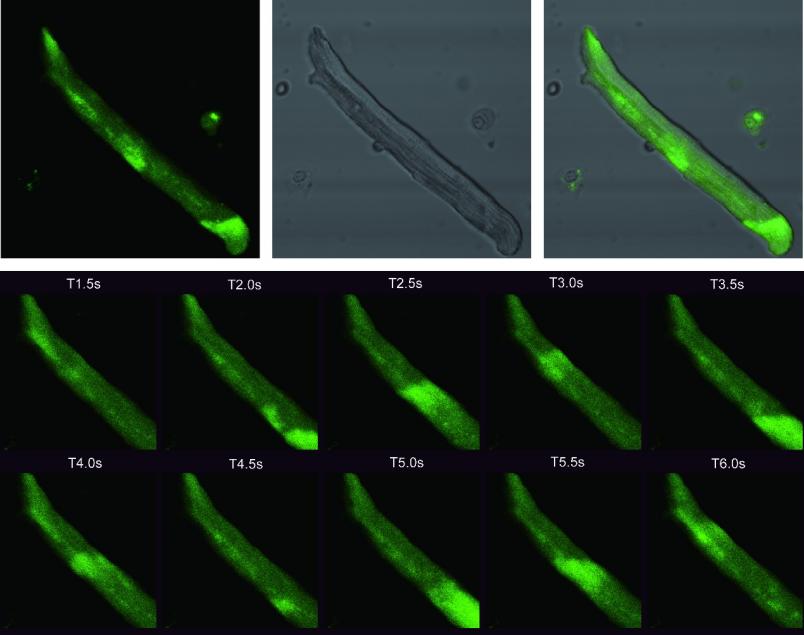

三等奖作品:《成年小鼠心肌细胞钙流成像》

作者:杨在明;指导老师:王楠

科学意义:心肌细胞是研究心脏结构、功能、药物作用机制以及药物研发的重要工具,而心肌细胞内的钙调控对于维持心脏和心肌细胞的正常生理功能有着重要作用。心肌细胞的兴奋引起胞膜上的电压依赖性L-型钙通道开放,胞外Ca2+内流,引起心肌细胞内钙库在短时间内向胞浆释放大量的钙,造成胞浆内钙离子浓度瞬时升高,即为钙瞬变。

图片创意:通过对钙瞬变的观测,可了解心肌细胞的功能活动特点和状态。本研究在原代提取的成体小鼠心肌细胞上负载钙指示剂(Fluo-3/AM),利用Olympus FV1000激光扫描共聚焦延时成像功能采集钙瞬变图像。